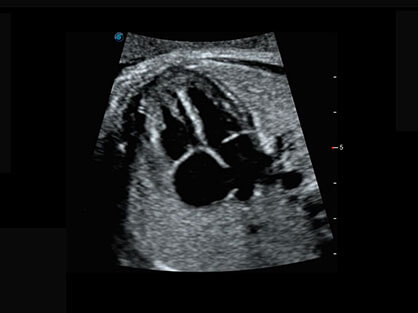

0.5mm厚度的薄层切片显像,可清晰显示微小病灶的连续断面。

宽频带腹部凸阵探头和腹部容积探头、大角度腔内探头和腔内容积探头、独特的生殖专用曲柄探头,为妇产应用提供全面诊疗方案。